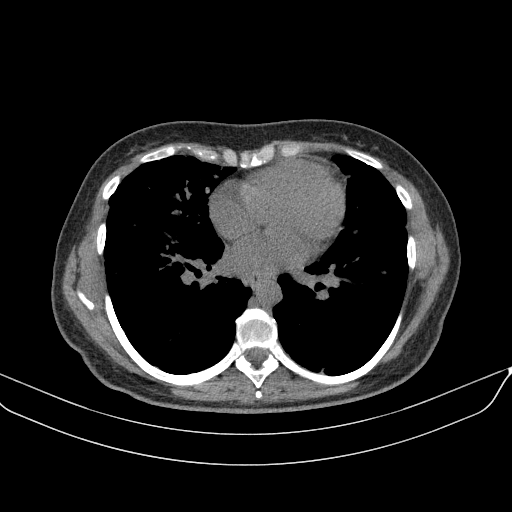

Targeted Slice 70 - Mediastinum Window Analysis (Generated vs Real Venous)

0.759

Mediastinum SSIM

45.2

Mediastinum RMSE

16.1

Mediastinum MAE

Average Mediastinum Window Metrics Across All Slices (40 slices) - Generated vs Real Venous

0.738

Mediastinum SSIM (Avg)

46.6

Mediastinum RMSE (Avg)

16.9

Mediastinum MAE (Avg)

Generated VENOUS CT scan (A→B translation)

Mediastinum window (WL 40, WW 400 β†’ Low βˆ’160, High +240)